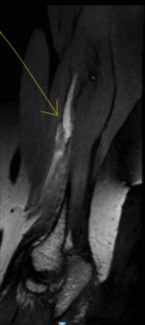

Because this tumor can be diagnosed with a computed tomography scan or magnetic resonance imaging, the excision of asymptomatic, small elastofibroma is not needed because malignant characteristics or transformation have never been reported. Radiotherapy could be an option for cases that are unresectable because of their localization.6

Our patient started to develop pain both during shoulder movement and during rest, so resection was the only choice. A parallel incision was made 2 cm under the scapula on both sides, and dissection through the latissimus dorsi was performed showing 2 tumors; both were round-shaped, adherent to the serratus muscle, and followed by marginal excision of the tumoral mass (Figure 3). Even if good hemostasis was achieved, 1 drain was placed on each side to mitigate the high risk of seromas and hematomas caused by the dead space and extensive dissection area. The drains were removed after 5 days when less than 50 mL per 24 hours were collected (Figure 4). During the 5 days of drainage, the patient received antibiotics and daily dressing changes.

Figure 4. The empty space left after resection of the right-side tumor. Some of the serratus muscle and ribcage can be observed.